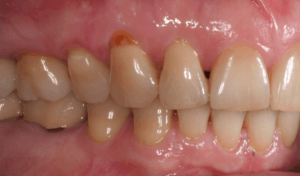

Для предварительной подготовки были привлечены пародонтолог и ортопед, поскольку отсутствие нескольких зубов, заболевание пародонта и дефекты твердых тканей зубов сопутствовали основной патологии. Проведены пародонтологические процедуры, вылечен кариес и его осложнения, изготовлены временные коронки для зубов с большим разрушением. На фото — временные коронки на боковых зубах.

Искривление окклюзионной кривой (плоскости смыкания зубов), возникшее в результате парадонтита, успешно удалось устранить, используя накусочные брекеты на верхних резцах и микроимплант, установленный во фронтальном участке нижней челюсти: